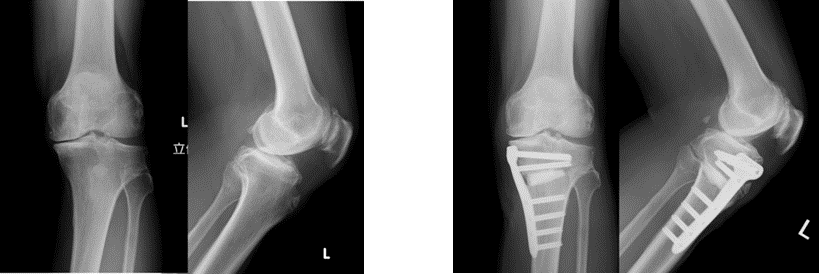

高位脛骨骨切り術 (high tibial osteotomy: HTO)

変形性膝関節症や大腿骨内顆骨壊死症などに適応があります。

脛骨の近位部を骨切りし、O脚に変形した下肢を軽度X脚に矯正し、荷重による負担を膝外側に移動することによって、膝内側の痛みを緩和する方法です。変形の程度によって開大式と閉鎖式骨切り術を使い分けております。

また、若年者で骨壊死を伴う症例には、骨軟骨片移植による関節内治療も併用し、良好な成績を得ています。